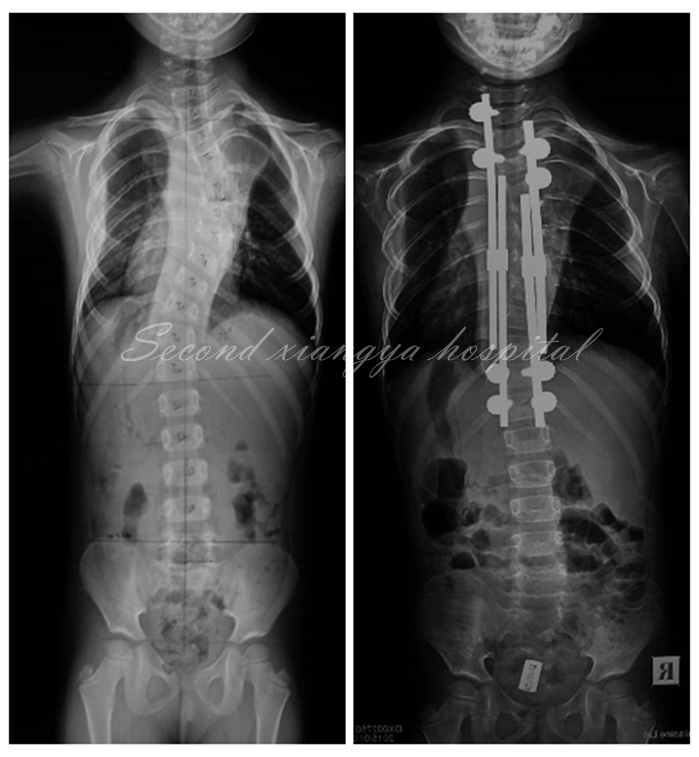

图3 6岁EOIS患儿,术前冠状面全脊柱正位X片(左),采用双生长棒技术,两端固定,顶椎撑开,术后6月复查正位X片(右)